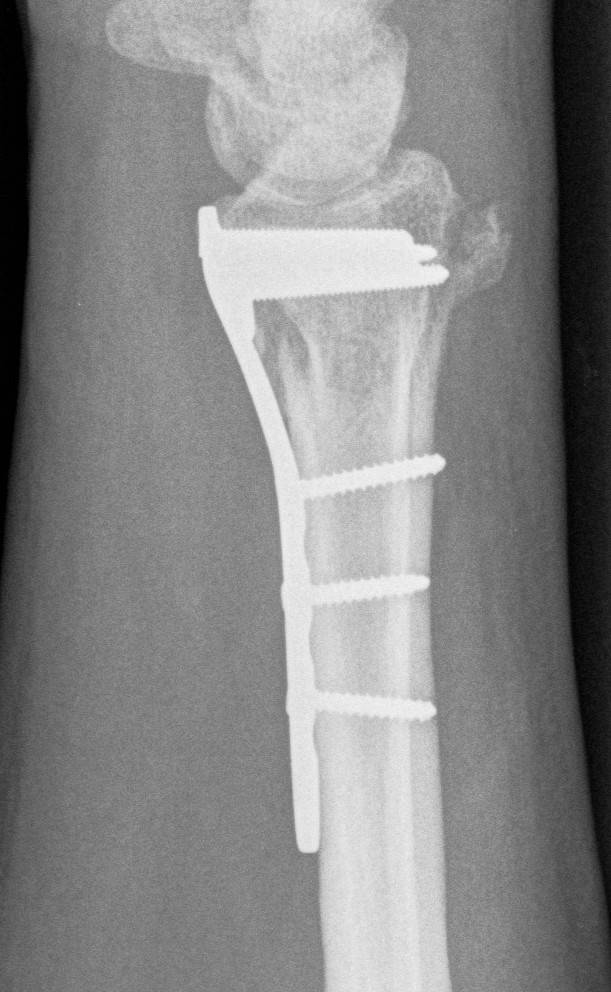

Dr shortDR short

Distal radius fracture with shortening and dorsal tilt